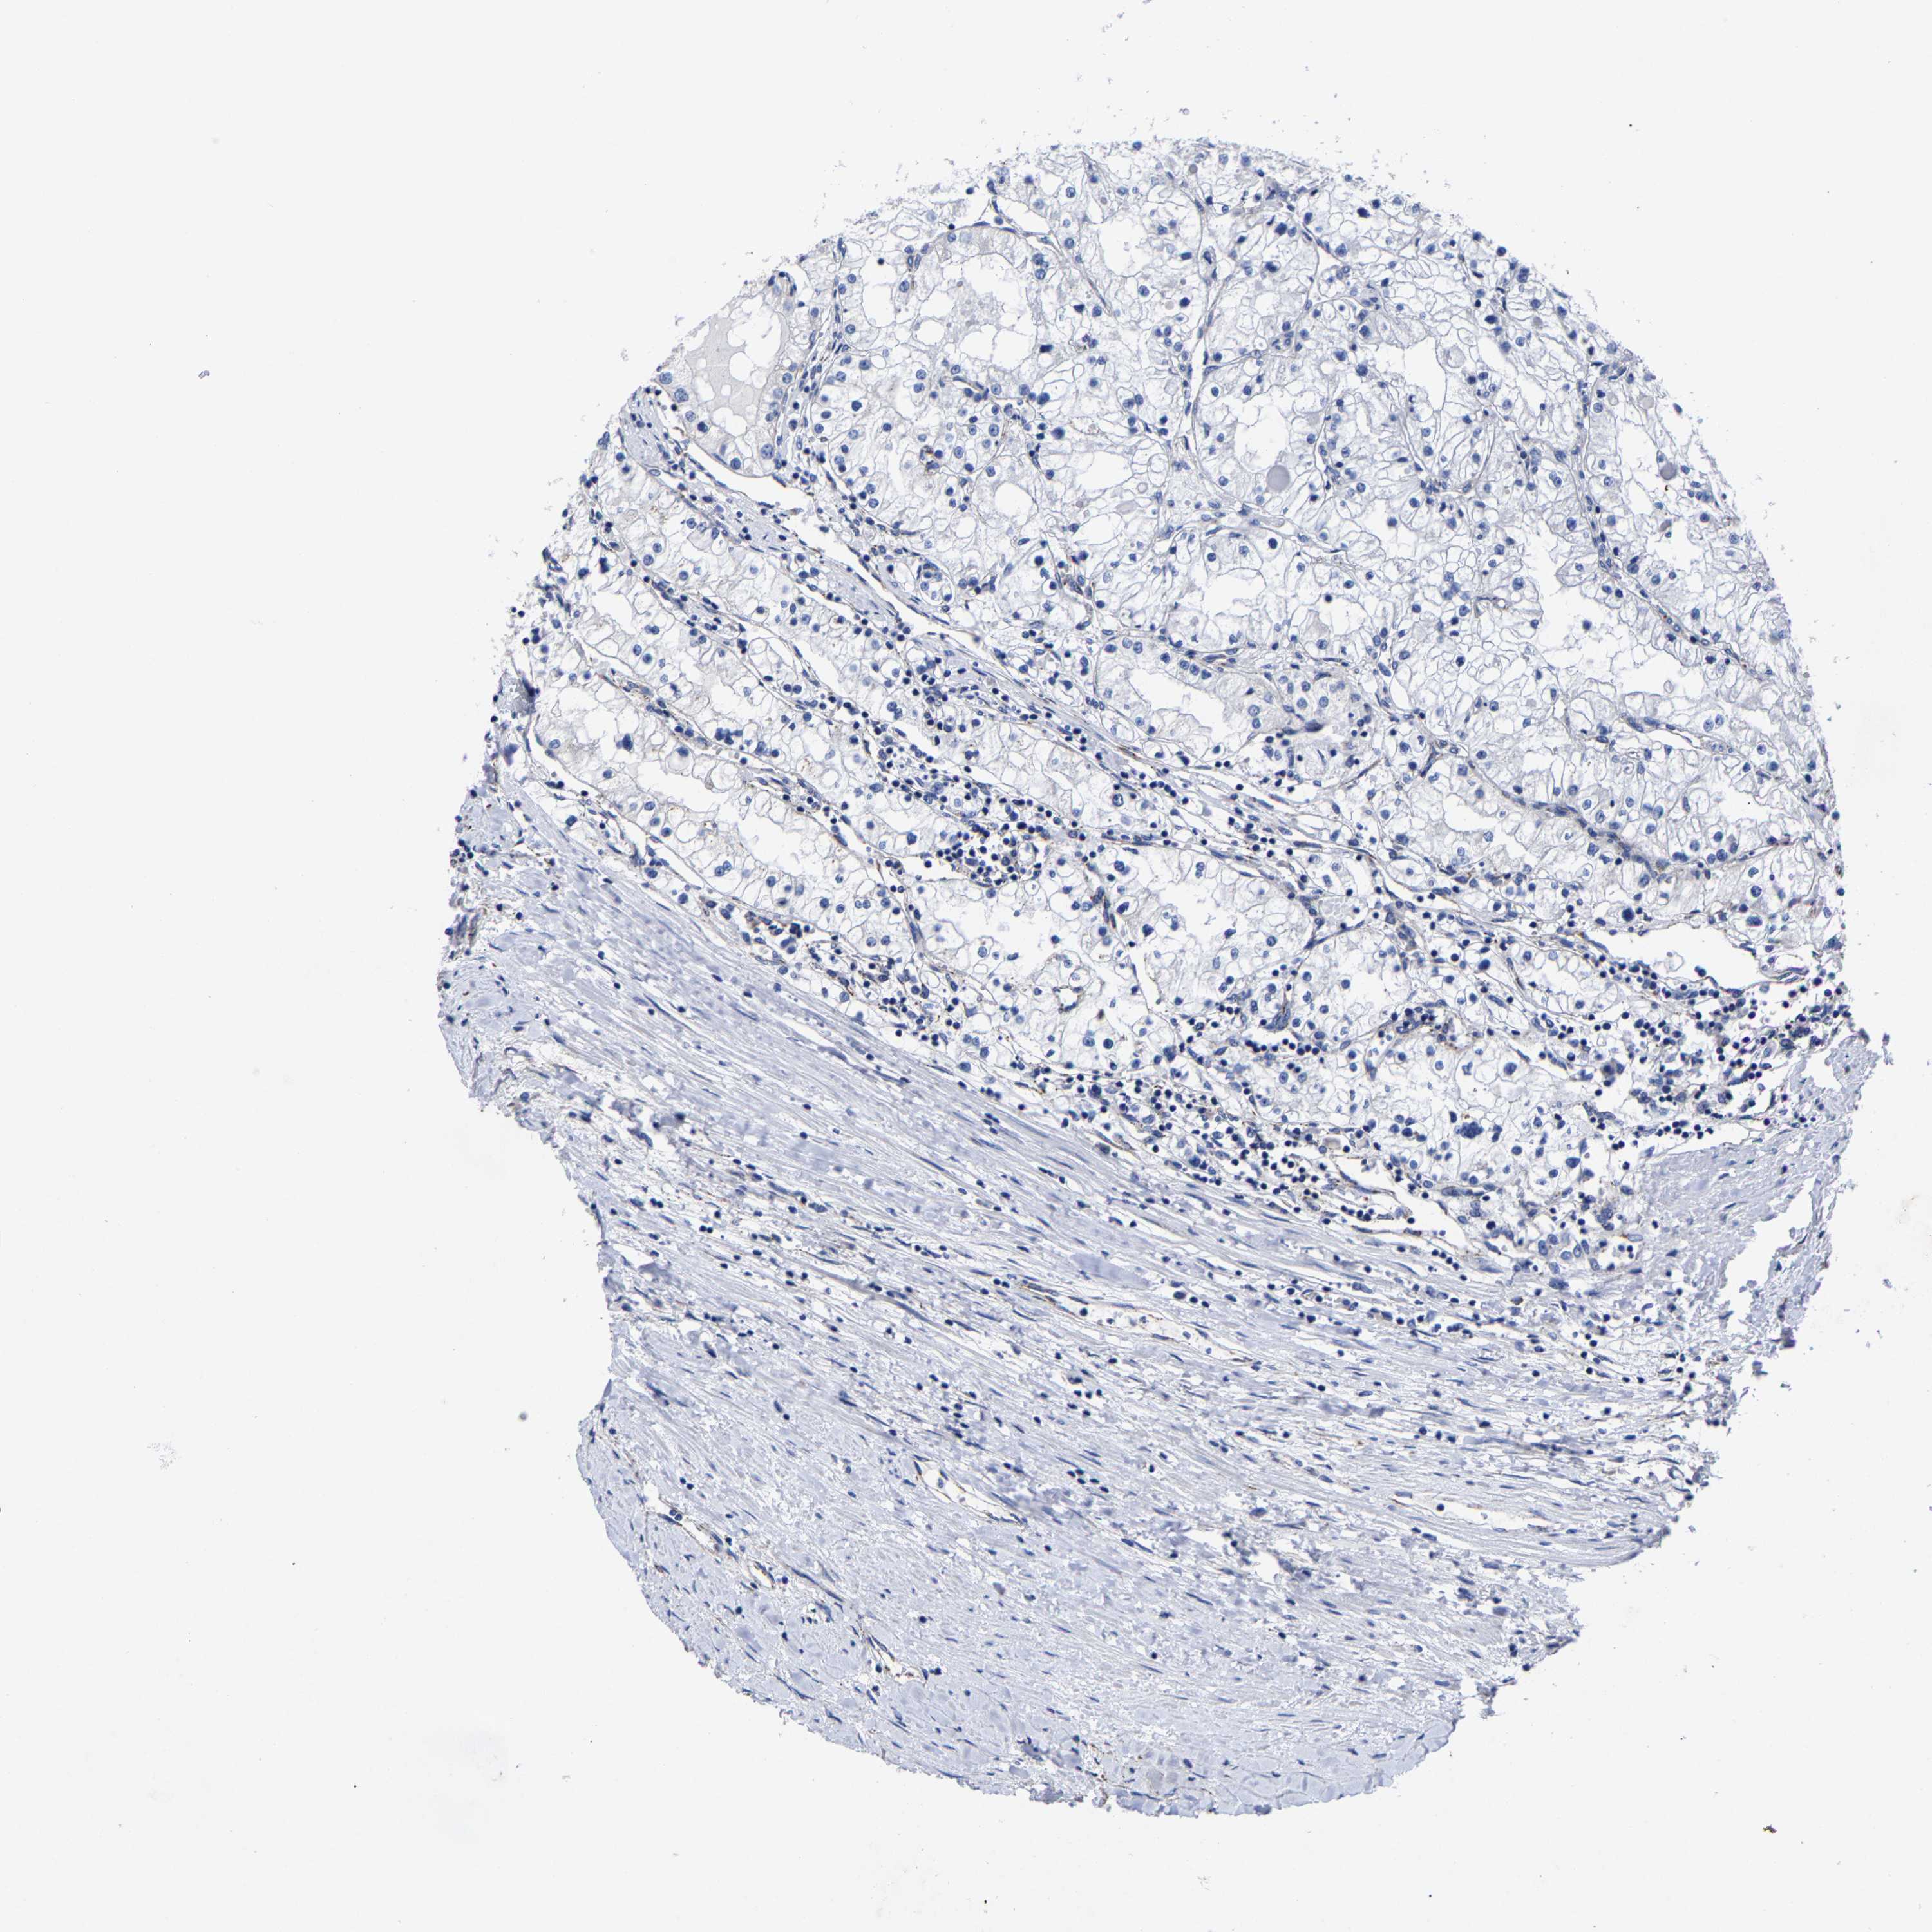

KIDNEY RENAL CLEAR CELL CARCINOMA (VALIDATION) - Interactive survival scatter ploti

The Survival Scatter plot shows the clinical status (i.e. dead or alive) for all individuals in the patient cohort, based on the same data that underlies the corresponding Kaplan-Meier plots. Patients that are alive at last time for follow-up are shown in blue and patients who have died during the study are shown in red.

The x-axis shows the expression levels (FPKM) of the investigated gene in the tumor tissue at the time of diagnosis. The y-axis shows the follow-up time after diagnosis (years). Both axes are complimented with kernel density curves demonstrating the data density over the axes. The top density plot shows the expression levels (FPKM) distribution among dead (red) and alive patients (blue). The right density plot shows the data density of the survived years of dead patients with high and low expression levels respectively, stratified using the cutoff indicated by the vertical dashed line through the Survival Scatter plot. This cutoff is automatically defined based on the FPKM cutoff that minimizes the p-score. The cutoff can be changed by dragging the vertical line or by entering a cutoff value in the square labeled "Current cut-off".

Under the Survival Scatter plot the p-score landscape (black curve; left axis) is shown together with dead median separation (red curve; right axis). Dead median separation is the difference in median mRNA expression between patients who have died with high and low expression, respectively. It is calculated as follows: median FPKM expression of dead patients with high expression - median FPKM expression of dead patients with low expression. This is intended to aid the user in visually exploring custom cutoffs and the associated p-scores and dead median separation.

Individual patient data is displayed and can be filtered by clicking on one or more of the category buttons on the top of the page. Categories describing expression level and patient information include: high, low, alive, dead, female, male and tumor stages. The scale of the x-axis can be toggled between linear and log-scale by clicking on the "x log" button. Mouse-over function shows TCGA ID, patient information and mRNA expression (FPKM) for each patient.

& Survival analysisi

Kaplan-Meier plots summarize results from analysis of correlation between mRNA expression level and patient survival. Patients were divided based on level of expression into one of the two groups "low" (under cut off) or "high" (over cut off). X-axis shows time for survival (years) and y-axis shows the probability of survival, where 1.0 corresponds to 100 percent.

AASS is potential prognostic, high expression is favorable in Kidney Renal Clear Cell Carcinoma (validation)

Best expression cut offi

Based on the FPKM value of each gene, patients were classified into two groups and association between prognosis (survival) and gene expression (FPKM) was examined. The best expression cut-off refers the FPKM value that yields maximal difference with regard to survival between the two groups at the lowest log-rank P-value. Best expression cut-off was selected based on survival analysis .

When clicking on this number, the vertical dashed line indicating cut-off, the interactive survival plot, and the Kaplan-Meier curve will be adjusted to show results based on the best expression cut-off.

: 2.36

TCGA RNA samplesi

RNA-seq data is reported as average FPKM (number Fragments Per Kilobase of exon per Million reads), generated by the The Cancer Genome Atlas (TCGA) .

Normal distribution across the dataset is visualized with box plots, shown as median and 25th and 75th percentiles. Points are displayed as outliers if they are above or below 1.5 times the interquartile range. FPKM values of the individual samples are presented next to the box plot.

Average pTPM 4.9

Number of samples 100